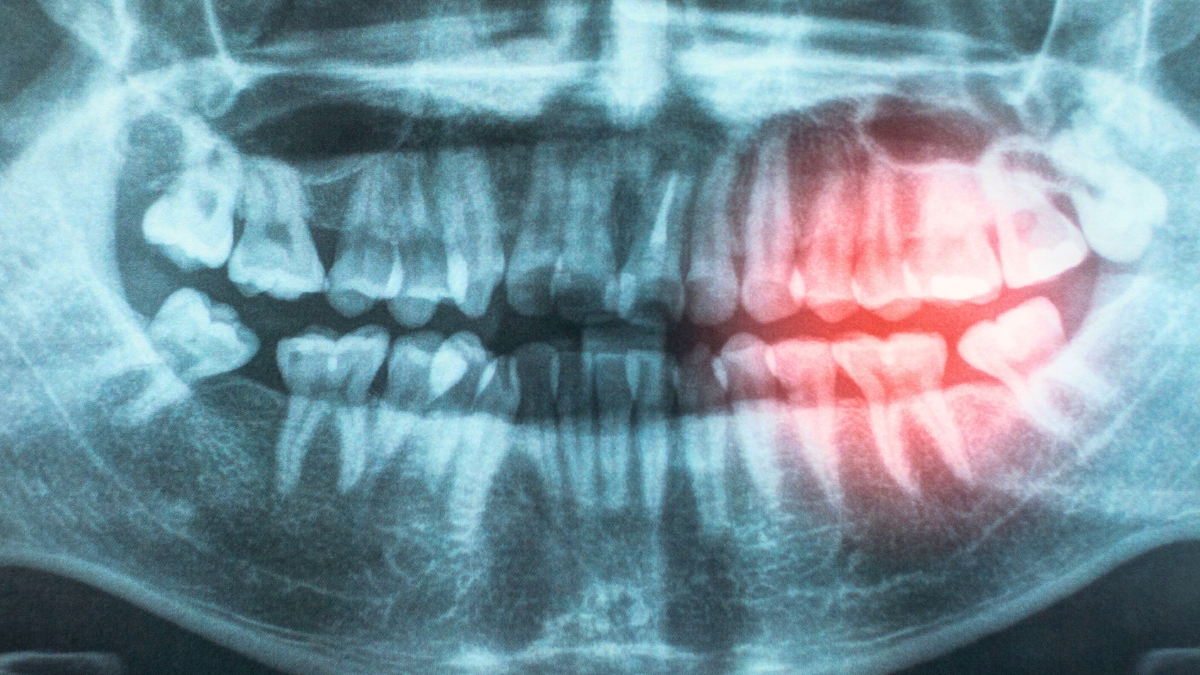

As part of their review, the researchers explored possible reasons for the association, including the likelihood that bacteria enter the body through exposed and damaged gums, contributing to chronic inflammation.

“Gum disease and poor oral hygiene can allow bacteria to enter the bloodstream, causing inflammation that may damage blood vessels and increase the risk of heart disease.”